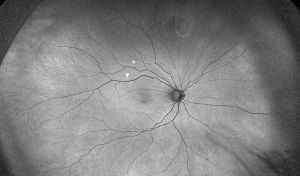

The diagnosis of retinal displacement is made by the presence of hyperautofluorescent lines on FAF imaging. These lines may be referred to as “retinal vessel printings” (RVPs) or retinal pigment epithelial vessel ghost lines” and are thought to indicate the original location of retinal vessels before retinal detachment.7